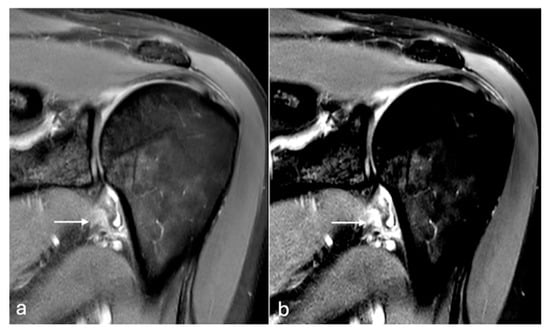

Figure 4. PDFS axial MR images of the right shoulder (a,b). Subtle early changes in muscle oedema in the infraspinatus muscle (arrow) are better detected on the image with modified windowing (b) when compared to default windowing (a). W/L of image (a)—1820/972, (b)—931/936.